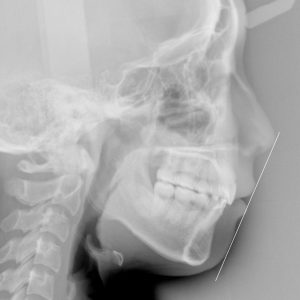

新着情報 982 治療後セファロ側面 – コピー Tweet 投稿日 : 2021年11月22日(月)カテゴリー : コメントを残す コメントをキャンセルメールアドレスが公開されることはありません。 * が付いている欄は必須項目ですコメント 名前 * メール * サイト 18歳 女性「 口もとを 下げたい 」( 上下顎前突症 ) ≫